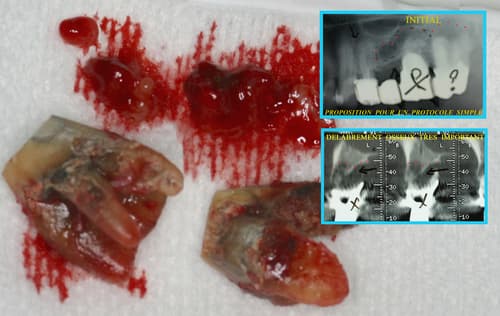

Le laser peut être utilisé dans la prise en charge des péri-implantites, avec un objectif de décontamination des tissus infectés autour des implants.

Pré-opératoire

Per-opératoire